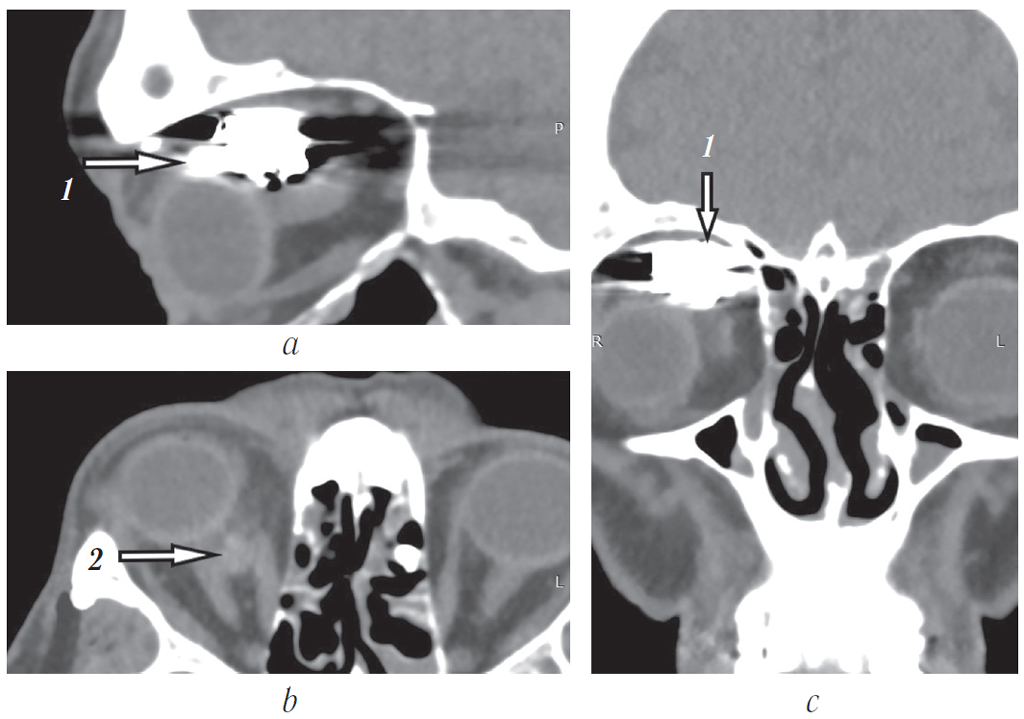

По данным КТ в полости правой глазницы от переднего верхнемедиального отдела до вершины глазницы располагается объёмное образование овальной формы, с чёткими ровными контурами размером 20,5 × 19 × 19 мм, плотностью 50–83 HU, интимно прилежащее к верхней прямой мышце, оттесняющее кпереди глазное яблоко и латерально — зрительный нерв (рис. 10).

При анализе КТ головы заподозрено наличие дефекта верхней стенки правой глазницы. По этому поводу пациент консультирован нейрохирургом.

Рис. 10. Компьютерная томограмма глазниц в сагиттальной (a), аксиальной (b) и корональной (с) проекциях. 1 — предполагаемое место дефекта верхней стенки глазницы, 2 — новообразование глазницы, 3 — тяж к новообразованию глазницы (указано стрелкой)

Fig. 10. Computed tomogram of the orbits in the sagittal (a), axial (b) and coronal (с) projections. 1 – suggested location of the upper orbital wall defect, 2 – orbital neoplasm, 3 – band to the orbital neoplasm (arrow)